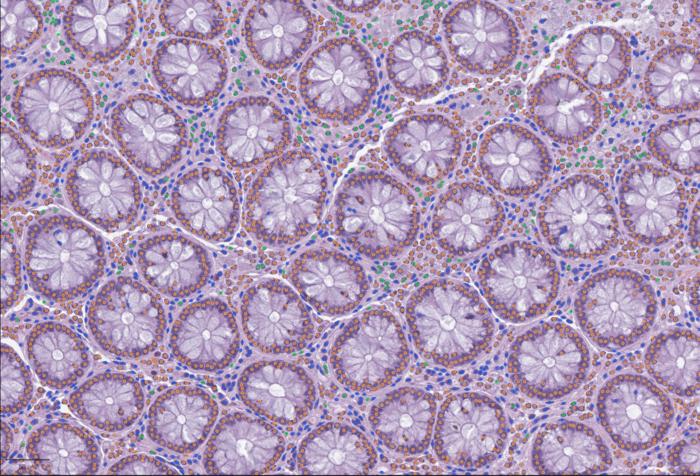

LazySlide is an open-source tool that uses AI to analyze large tissue images, linking visual patterns with molecular data. Histopathological data remain one of the most trusted tools in science when doctors or researchers want to understand what’s happening inside a tissue. Today, they have largely gone digital. These images, therefore, contain enormous information about... [3833 chars]